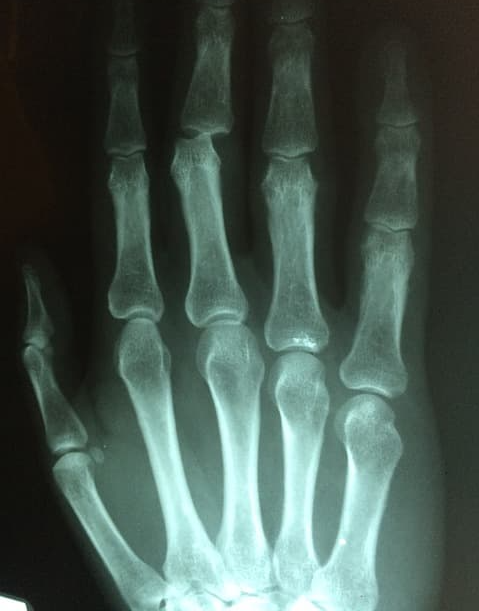

퇴행성 관절염은 연골손상과 뼈의 변형이 주원인이기 때문에

상태를 확인하기 위해 X-ray검사를 하고

류머티즘 관절염 증상은 혈액검사를 해서 염증수치를 확인하게 됩니다.